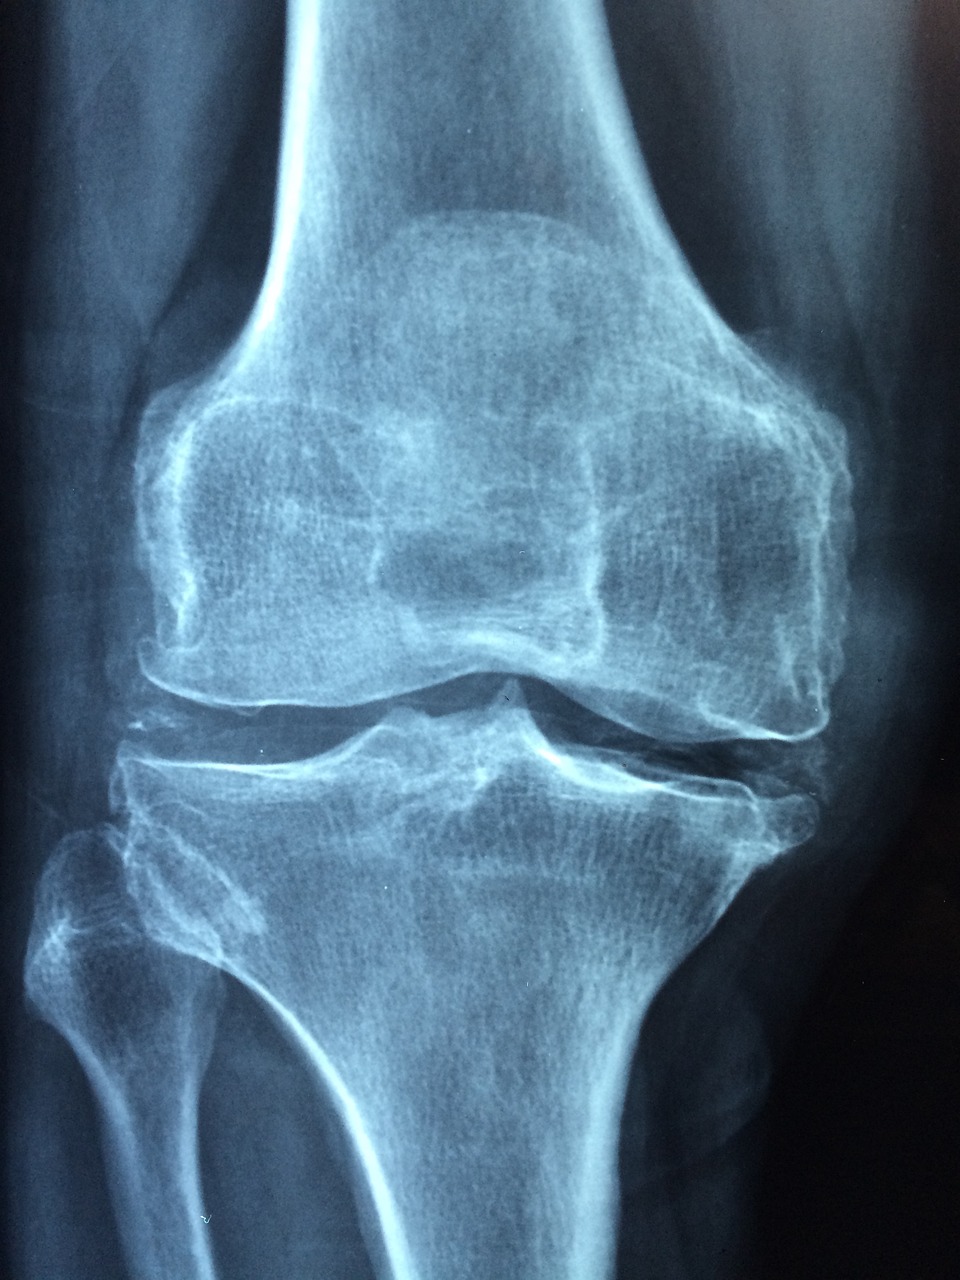

나이가 들면서 우리 몸은 다양한 변화를 겪으며, 그중에서도 골밀도 감소는 노화의 대표적인 증상 중 하나입니다. 골밀도란 뼈의 강도와 밀도를 의미하며, 일정 수준 이하로 낮아지면 뼈가 약해지고 쉽게 부러질 위험이 커집니다. 이러한 현상은 특히 중장년층에서 두드러지게 나타나며, 골다공증이라는 질환으로 이어질 수 있습니다.

골다공증은 뼈조직이 점차 감소하고 구멍이 많아지는 질환으로, 작은 충격에도 골절이 발생할 가능성이 높아지는 것이 특징입니다. 이러한 골다공증의 주요 원인은 여러 가지가 있지만, 가장 대표적인 요인은 호르몬 변화입니다. 특히 여성의 경우 폐경 이후 에스트로겐 수치가 급격히 감소하면서 골밀도가 빠르게 줄어드는 경향이 있습니다. 에스트로겐은 뼈의 칼슘 흡수를 돕고 골밀도를 유지하는 중요한 역할을 하는데, 폐경 이후 이 호르몬이 감소하면서 뼈가 약해지는 것입니다.